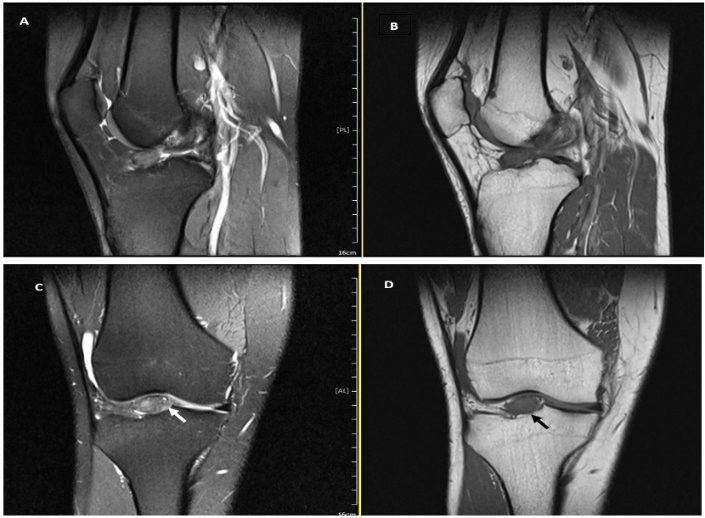

A 21-year-old male patient presented to our orthopedic department with a 4-year history of vague right knee pain. The patient’s pain was aggravated while climbing the stairs and squatting. He denied any previous trauma to the knee and he had no complaints of instability. On physical examination, there was no swelling or tenderness over the joint line, the range of motion was full, and pivot shift test and Lachman test were negative. Routine blood test results were unremarkable, X-ray views of the knee were unremarkable, and the T1 and T2 weighted magnetic resonance imaging (MRI) revealed a well-circumscribed solid lesion, measuring about 14×11 mm, arising from the tibial attachment of the anterior cruciate ligament (ACL) (Figure 1).

Figure 1: A-D) MRI of the right knee joint showed a well circumscribed mass, which is localized on the tibial attachment of the anterior cruciate ligament. In T2W MRI (A & C) the signal intensity of the tumor was hyperintense. While, in T1W MRI (B & D) the tumor showed an isointense signal compared to muscle. MRI= magnetic resonance imaging.